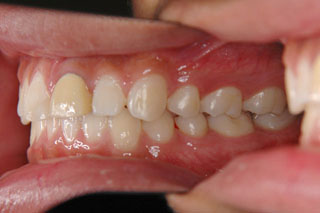

2年半ほどの治療で、装置を撤去し保定治療に移行しています。飛び出ていた前歯も、下の歯と正しく噛めるようになりました。口元の突出も消え、口唇閉鎖時に前歯が覗いて見えるという事も無くなりました。

保定治療に移行してから3年半が経過しました。上の顎に生えてきた親不知は下の顎の奥歯と噛み合うようになりましたが、下の親不知は、斜めに埋まっていましたので、噛み合わせへの変化を防止するためにも早めに抜いて貰いました。矯正治療ではなるべく長期に渡って、管理を行いますが、2年3年と大きな変化が無く、緊密な噛み合わせが確保出来ていれば、将来的にも安定が期待出来ると思います。